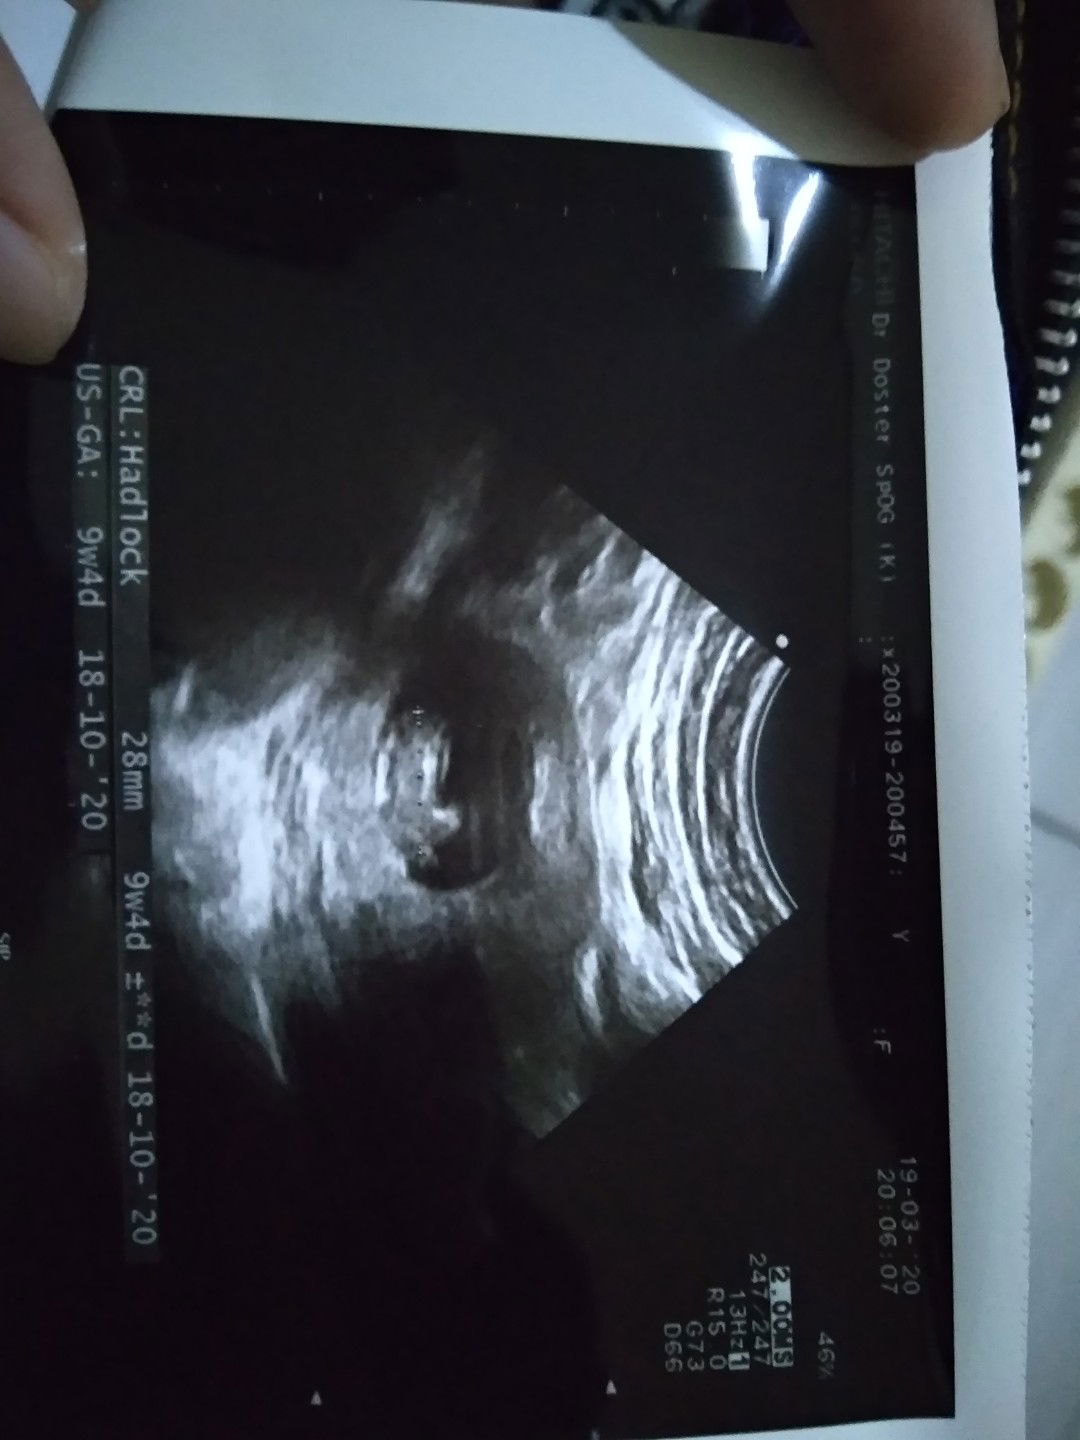

Usg lagi..

Alhamdulillah bun hari ini menjawab kekhawatiran saya tgl 15 kemarin .. Saya seneng banget?? Jangan ragu cari second opinion ya bun?

USG tapi kosong

Bun.. Saya kemarin usg di bidan, tapi kata dokternya rahim saya kosong, gimna ya bun? Pdahal saya sudah tespack positif , sepulang usg pun saya test lagi dan positif. Saya juga ngerasa kadang mual, sering buang air kecil, pusing, telat haidnya 9 januari kalo dihitung pke aplikasi sekitar 9 mingguan. Saya shock waktu dibilangin gitu dan disuruh usg 2 minggu lagi. Mau ke dokter usg nya masih nunggu akhir bulan biar sekalian. Ada yg pernahkah?